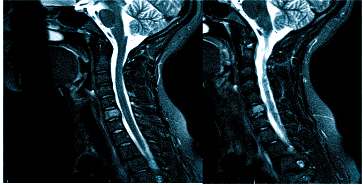

Если оно не дает необходимой картины по проблеме, то может быть назначена , а также: МРТ шейного отдела позвоночника

Важно! Если даже после подобной процедуры не станет ясна причина боли в голове, то потребуется дополнительная диагностика в виде МРТ, но уже позвоночника тела человека, а именно его шейного отдела.

МРТ при головных болях (в трех проекциях): специальная программа выстраивает объемные изображения полученных срезов, что позволяет увидеть даже мельчайшие изменения и отдифференцировать патологию от нормы

Выделяют несколько видов магнитно-резонансной томографии головы: нативную, усиленную контрастным препаратом и сканирование в ангиорежиме. К каждому исследованию есть свои показания, поэтому ответить на вопрос: “Какую МРТ делать при головной боли?” — не всегда возможно. Врач выбирает нужный тип диагностики, опираясь на клиническую картину. В оценке опухолевых новообразований и для определения стадийности (в том числе — метастатического распространения) используют МРТ с контрастированием. Введение препаратов на основе хелатов гадолиния позволяет рассмотреть даже небольшие опухоли в труднодоступных местах, поэтому магнитное сканирование с усилением с успехом применяют, если прочие способы визуализации показали неоднозначные результаты. При подозрении на сосудистое заболевание головного мозга оптимальным выбором будет проведение сканирования в ангиорежиме.